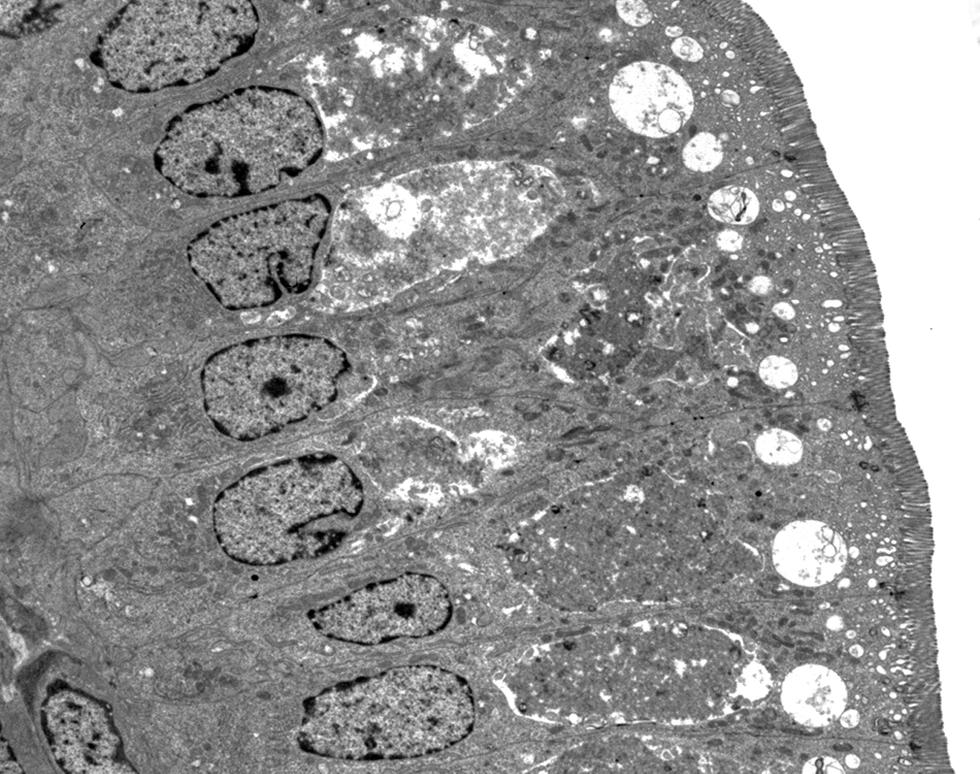

Intestinal mucosa